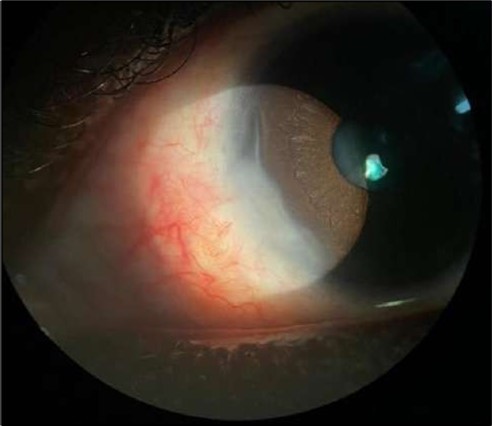

On the current presentation, Snellen VA was 6/6 in the right eye and 6/9 in the left eye, with normal IOP. The left eye demonstrated mild upper lid edema and intense nasal ciliary injection. Slit-lamp evaluation revealed a crescentic area of stromal corneal melting between 7 and 10 o’clock nasally, with overhanging edges and a fluorescein-positive base. No corneal infiltrates were present, and the surrounding stroma remained clear. The anterior chamber was deep and quiet, lens was transparent, pupil was round and reactive & normal posterior segment. Anterior segment optical coherence tomography (AS-OCT) confirmed a localized ulcer, measuring 1324 µm in horizontal width and extending to a depth of 380 μm, compared with an adjacent healthy corneal thickness of 824 µm, corresponding to approximately 46.1% stromal thinning (Figure 1a, Figure 1b, Figure 1c)

Figure 1a.Left eye (OS), on presentation. Slit-lamp image: crescent-shaped peripheral corneal ulceration located nasally, with severe adjacent conjunctival injection, peripheral thinning, and stromal infiltration.

Left eye (OS), on presentation. Slit-lamp image: crescent-shaped peripheral corneal ulceration located nasally, with severe adjacent conjunctival injection, peripheral thinning, and stromal infiltration.